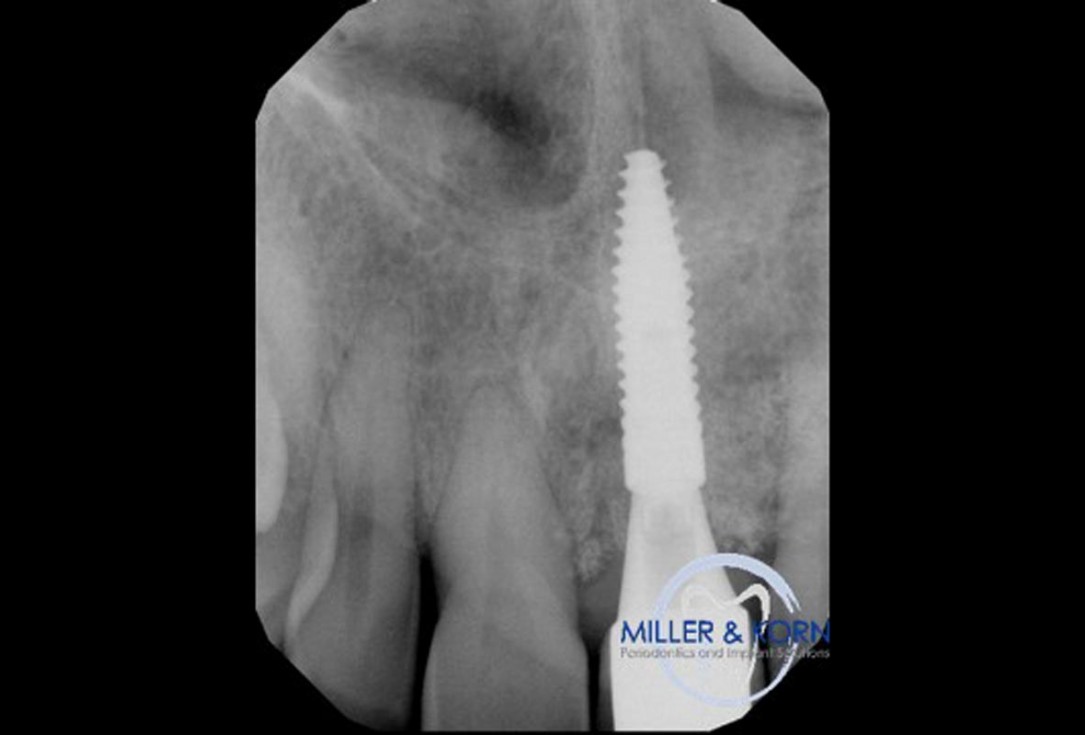

35/39 - Immediate post surgery radiographImmediate implant placement and correction of horizontal and vertical bone loss using an allograft bone ring, cerabone® and Jason® membrane - Drs. Miller and Korn